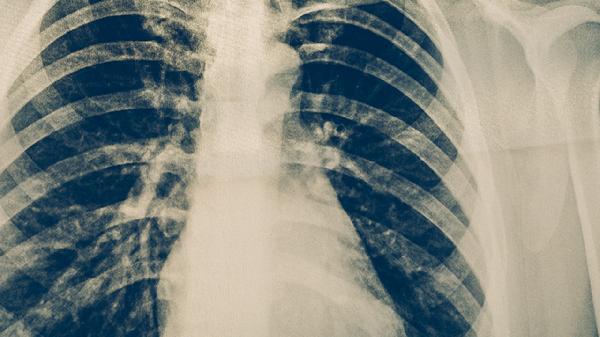

间质性肺炎的CT表现主要有毛玻璃样影、网格状影、实变影、支气管血管束增粗、蜂窝状改变等。

毛玻璃样影在CT图像上表现为肺部密度轻度增高,但其内的支气管血管束仍可清晰显示。这种征象通常出现在间质性肺炎的早期阶段,反映了肺泡间隔的轻度增厚或肺泡腔内少量液体渗出。毛玻璃样影的分布可为弥漫性、斑片状或地图状,常见于过敏性肺炎、非特异性间质性肺炎等类型。随着病情进展,毛玻璃样影可能转化为网格状影或实变影,需要定期随访观察变化。

网格状影是由小叶间隔增厚和interlobularseptalthickening形成的细线状阴影,在CT上呈现为网状结构。这种表现多见于肺野周边部和基底部,是肺间质纤维化的早期征象之一。网格状影可分为finereticulation和coarsereticulation两种类型,细网格通常代表活动性炎症,而粗网格则提示已形成纤维化。特发性肺纤维化患者的网格状影常伴有牵拉性支气管扩张。

实变影表现为肺组织密度均匀增高,完全掩盖其内的血管纹理。这种征象表明肺泡腔内充满炎性渗出物、细胞或其他物质,是间质性肺炎急性加重期的典型表现。实变影的分布特点有助于鉴别诊断,如机化性肺炎多表现为游走性实变,而寻常型间质性肺炎的实变通常局限。实变影的出现往往提示需要更积极的治疗干预。

支气管血管束增粗是指CT图像上支气管壁和伴随血管的周围间隙增厚。这种表现源于支气管血管周围间质的炎症细胞浸润和纤维组织增生。支气管血管束增粗可伴有支气管扩张或变形,在淋巴管平滑肌瘤病和结节病中尤为明显。这种征象的演变过程可以反映治疗效果,有效的治疗可使增粗的支气管血管束逐渐恢复正常。

蜂窝状改变是间质性肺炎的晚期表现,CT上显示为簇状分布的囊性气腔,壁厚且清晰。蜂窝肺通常位于胸膜下区,大小从数毫米至数厘米不等,代表不可逆的肺结构破坏和纤维化。这种改变最常见于寻常型间质性肺炎,表明疾病已进入终末期。蜂窝状改变的范围和分布对预后评估具有重要意义。